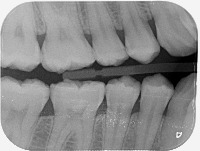

Caries Dentaires Computer Vision Project

Dental Health Diagnosis: Healthcare professionals can use the model to facilitate the early detection and categorization of caries dentaires, helping them identify the severity of the decay, and plan the most effective treatment.

Dental Education: Dental schools can use the model as a teaching tool, helping students understand the different stages of tooth decay and honing their diagnostic skills through digital practice cases.

Dental Insurance Assessment: Insurance companies can use the model to categorize the severity of customers' dental issues, aiding them in creating more comprehensive and accurate coverage plans.

Dental Research: Researchers studying oral health can use the model in their studies to better understand the progression of tooth decay and develop new treatments or prevention methods.